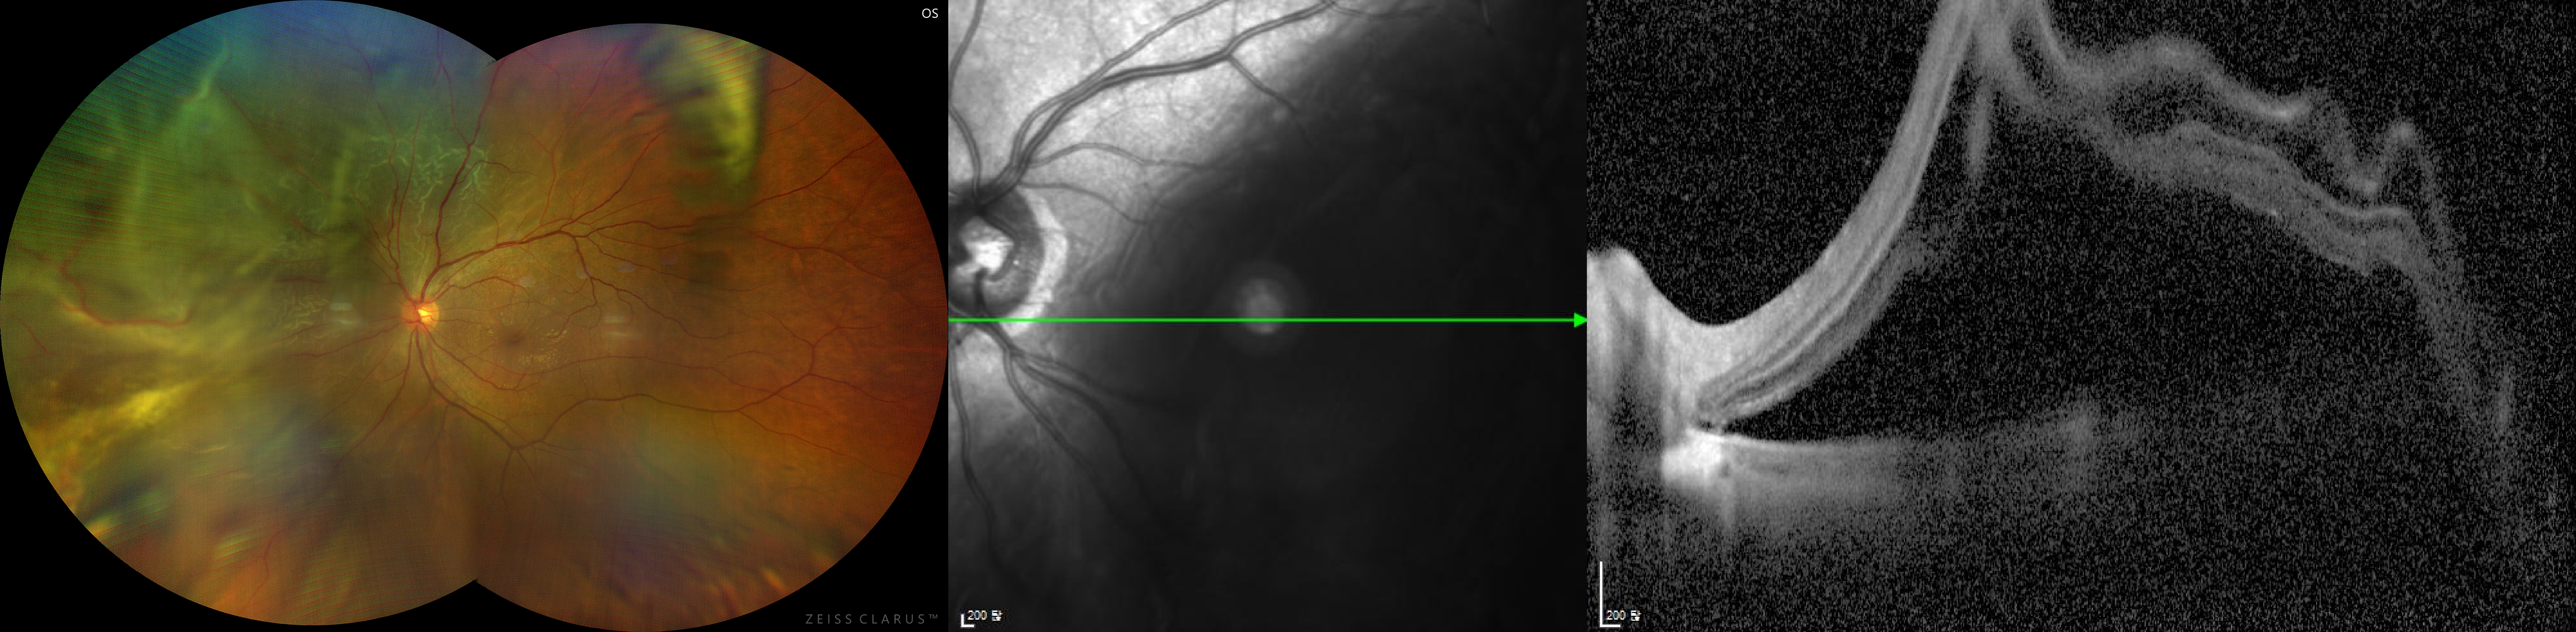

망막박리

상이 맺혀 필름의 역할을 수행하는 눈의 가장 안쪽 부분인 망막이 찢어지면

시야 결손 현상이 생기다가 심할 경우 실명으로 이어질 수 있습니다.

망막박리 수술 전 사진

망막박리 수술 후 사진

망막박리 치료와 예방

망막박리가 진행되지 않은 망막열공의 경우, 추가 진행을 막기 위해 레이저 치료를 이용하나

이미 망막박리가 진행되었다면 수술을 해야 합니다.

수술은 공막돌륭술과 유리체 절제술, 두 가지 방법 중 환자의 상태에 맞춰 진행됩니다.

유리체 절제술

망막박리 치료

공막돌륭술